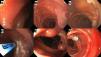

She was admitted to the emergency service with profuse melena and severe microcytic-hypochromic anemia, with a hemoglobin level of 3.5 g/dl. Liver function tests were normal and anti-tissue transglutaminase testing was negative. The patient rejected the use of blood products and so was managed with intravenous iron (1,000 mg of ferric carboxymaltose) plus subcutaneous epoetin alfa (4,000 IU/day for 10 days). Neither esophagogastroduodenoscopy (EGD) nor initial colonoscopy revealed the origin of the bleeding. The endoscopies were repeated at our center, identifying a prominent submucosal vascular network in the duodenum, terminal ileum, and colon, with no active bleeding (Fig. 1A-E). Computed tomography (CT) angiography was normal. Video capsule endoscopy (VCE) revealed multiple small bowel angiodysplasias and phlebectasias (Fig. 1F). Anterograde deep enteroscopy with a single balloon showed distal angiodysplasias and phlebectasias, with red dots, in the jejunum, that were treated using argon plasma coagulation (APC) (Fig. 2A-D). Endoscopic clips were installed in one of the dilated vessels due to bleeding (Fig. 2E and F). Patient progression was favorable, with no new bleeding episodes. Upon her discharge, the patient’s hemoglobin level was 8.5 mg/dl; it was 13.5 mg/dl at the follow-up at three months.

Esophagogastroduodenoscopy, colonoscopy, and video capsule endoscopy (VCE) images showing vascular abnormalities. (A) Prominent submucosal vascular network in the duodenal bulb. (B) Phlebectasias in the second part of the duodenum. (C) Prominent submucosal vascular network in the terminal ileum. D) Phlebectasias in the transverse colon. (E) Prominent submucosal vascular network in the colon. F) The VCE image shows a small angiodysplasia with no active bleeding.